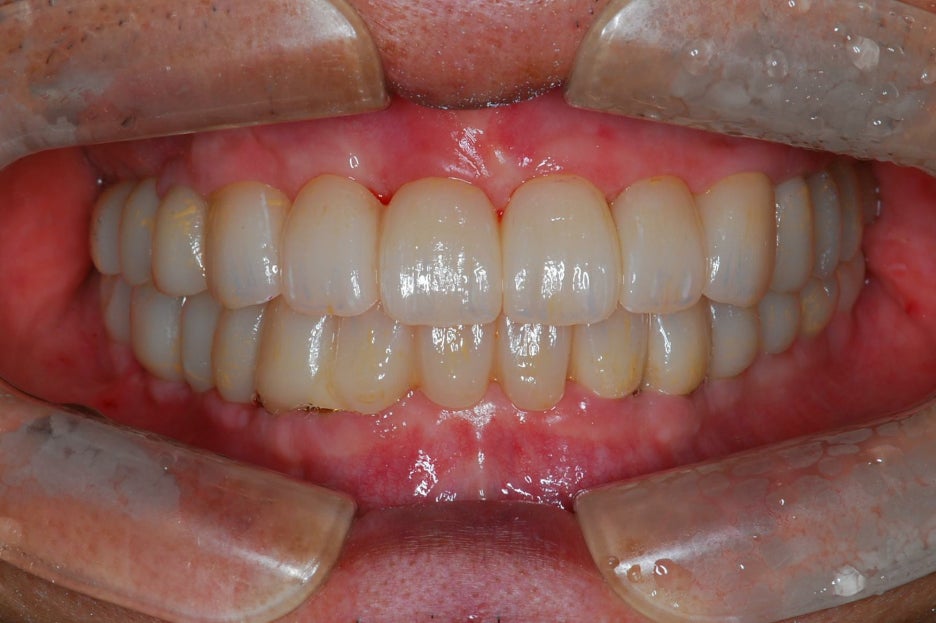

무치악환자를 위한 전악임플란트

전악임플란트 중점 치료

<참고이미지> 무치악 환자의 임플란트 치료 사례 / 환자에 따라 치료결과는 다를 수 있으며 임플란트 주위염 등이 발생할 수 있습니다.

무치악 환자에게 적용시 치아의 기능을 일정수준으로 회복할 수 있는 치료입니다.

20.09.19 경과체크 / 무치악 임플란트 치료 / 환자에 따라 치료결과는 다를 수 있으며 임플란트 주위염 등의 부작용이 발생할 수 있습니다.

기능의 회복은 물론 심미적인 목적도 충족 시킬 수 입니다.